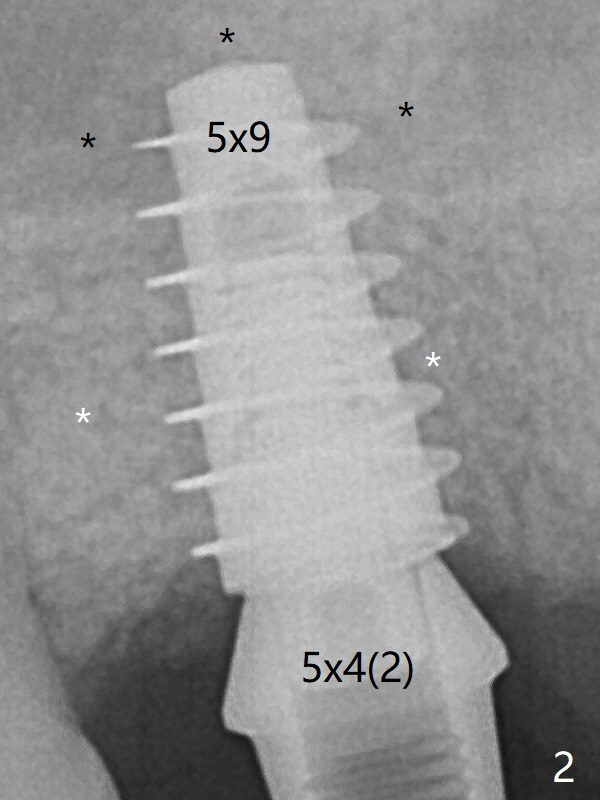

After placing bone graft into the sinus and the osteotomy (Fig.2 black *), a 5x9 mm implant is placed with >30 Ncm.  Second round of bone graft is placed around the implant, including DB defect (white *).  Then a 5x4(2) mm pair abutment is placed, followed by the third round of bone graft (Fig.3 *).  If the abutment were placed prior to the 2nd round of the bone graft, the latter would be unable to reach the deepest implant threads or the defect.